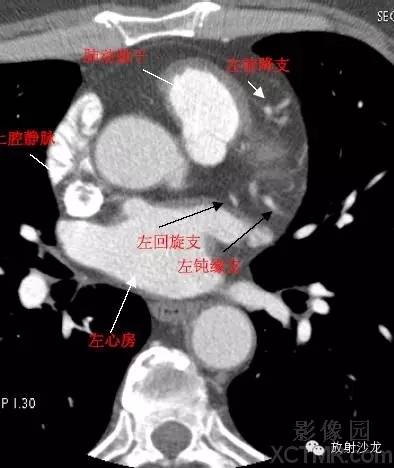

SVC –Superior Vena Cava上腔静脉

LMA -Left Main Artery冠状动脉左主干

LAD -Left Anterior Descending Artery左前降支

LCX -Left Circumflex Artery左回旋支

LMB -Left Obtuse Marginal Branch 左边缘支(钝缘支)